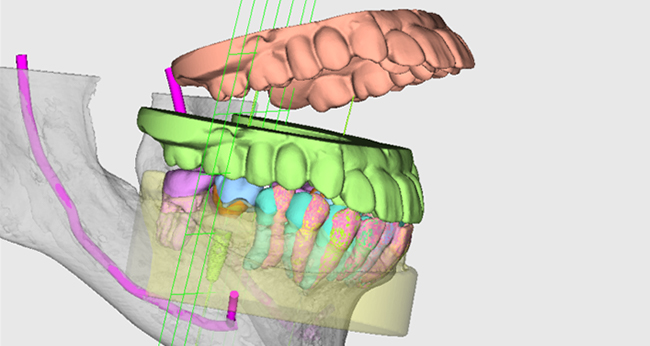

開院以来、年間平均130件以上、法人全体で、インプラント合計本数1,600本以上の治療実績があります。その全ての症例で、歯科用CTを使用して患者様の骨の状態を確認し、丁寧にカウンセリングを行った上で治療を行っております。

「ノーベルガイド」は、歯肉を切開せずにインプラントを埋入するノーベル独自のガイドシステムです。術前のデジタルシミュレーションとガイドテンプレートで正確な埋入と低侵襲な手術を実現し、患者様のご負担を軽減します。